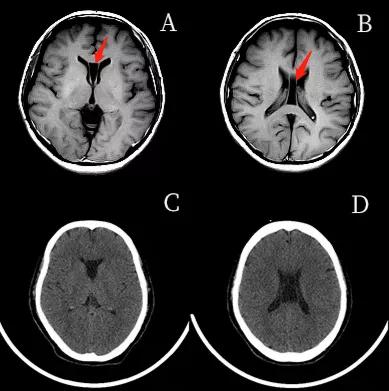

透明隔腔(CSP) 的前上方为胼胝体,后下方为穹隆。侧壁即透明隔小叶。透明隔腔≤3mm,描述可见透明隔腔。

1.胼胝体膝部;2.透明隔腔;3.穹隆柱;4.穹隆体;5.穹隆脚;6. Vergae腔;7.胼胝体压部

透明隔腔增宽是透明隔腔≥3mm,直径<10mm,描述可见透明隔腔增宽,透明隔的两壁呈前后平行排列,边界清晰,或内凹,对周围组织无压迫,为正常生理变异,临床无症状。透明隔腔≥10mm,描述可见透明隔腔明显增宽。

两壁呈前后内凹

两壁呈前后平行